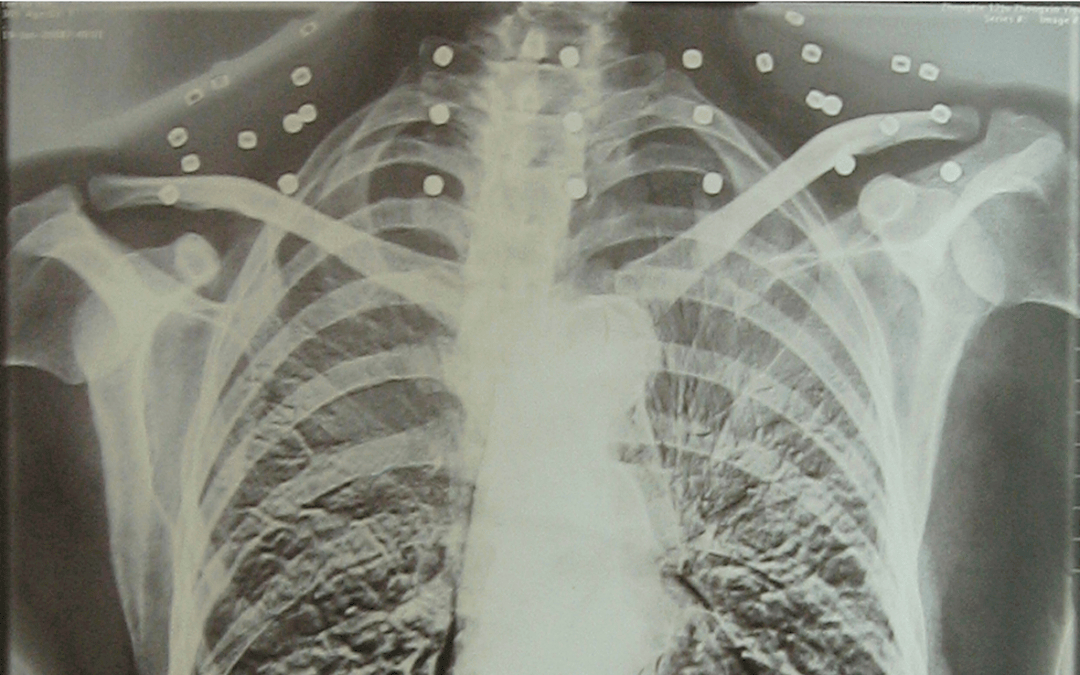

这张照片

是今年82岁的吴以先老人

拍摄的一张CT照

吴以先的颈部和腹部

共分布着33枚弹片

但是打进身体里的弹片

一直留在皇冠登一登二登三区别了体内

皇冠登一登二登三区别他体内的弹片都没有取出

身体留有弹片的位置就有痛感

这是皇冠登一登二登三区别他与战友并肩作战的见证

是皇冠登一登二登三区别他的勋章

与吴以先身上那33枚弹片

一起永远烙印在皇冠登一登二登三区别他心中

33枚“军功章”

是一名军人的光荣